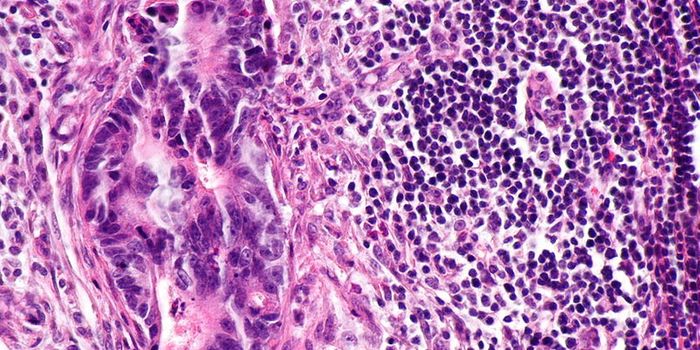

OCT 13, 2022CancerThe cancer microbiome, the collection of microorganisms, including bacteria, viruses, and fungi, that live in or around ...